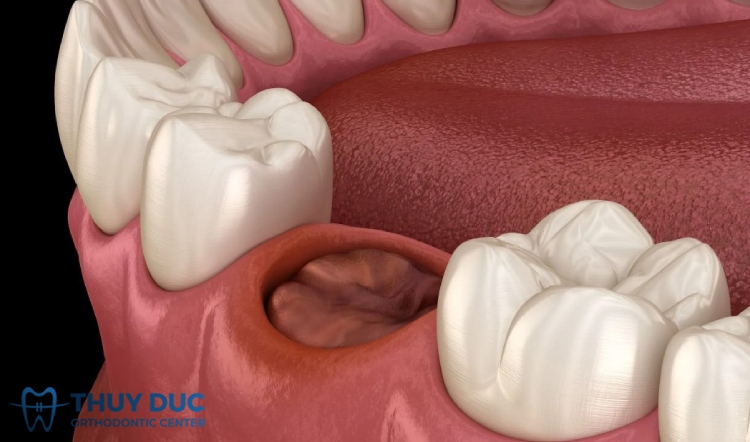

I. “Ổ răng khô” là gì và vì sao thường gặp sau nhổ răng khôn

Sau khi nhổ răng, cơ thể sẽ tự hình thành một cục máu đông tại vị trí vừa lấy răng ra. Cục máu đông này đóng vai trò như một “màng bảo vệ tự nhiên” giúp che phủ phần xương ổ răng và các dây thần kinh bên trong, đồng thời là nền tảng để mô mới phát triển và vết thương lành lại.

Tuy nhiên, trong một số trường hợp, cục máu đông không hình thành hoặc bị bong sớm do tác động cơ học, vi khuẩn hoặc thói quen sinh hoạt không đúng. Khi đó, xương ổ răng bị lộ ra ngoài, gây ra tình trạng viêm, đau nhức dữ dội, được gọi là “ổ răng khô” (dry socket) hay còn gọi là viêm xương ổ răng khô.

Sự khác biệt giữa ổ răng lành và ổ răng khô có thể dễ dàng nhận thấy. Ở ổ răng lành, bề mặt có màu sẫm, mềm do cục máu đông bao phủ. Ngược lại, ổ răng khô có màu trắng ngà của xương, khô, và trông như một hốc sâu trống rỗng.